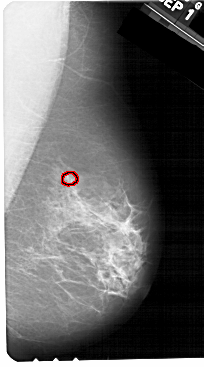

A_1328_1.RIGHT_CC

RIGHT_CC LINES 5491 PIXELS_PER_LINE 3016 BITS_PER_PIXEL 12 RESOLUTION 43.5 OVERLAY

FILE: A_1328_1.RIGHT_CC.OVERLAY

TOTAL_ABNORMALITIES 1

ABNORMALITY 1

LESION_TYPE CALCIFICATION TYPE PLEOMORPHIC DISTRIBUTION CLUSTERED

ASSESSMENT 4

SUBTLETY 5

PATHOLOGY BENIGN

TOTAL_OUTLINES 1